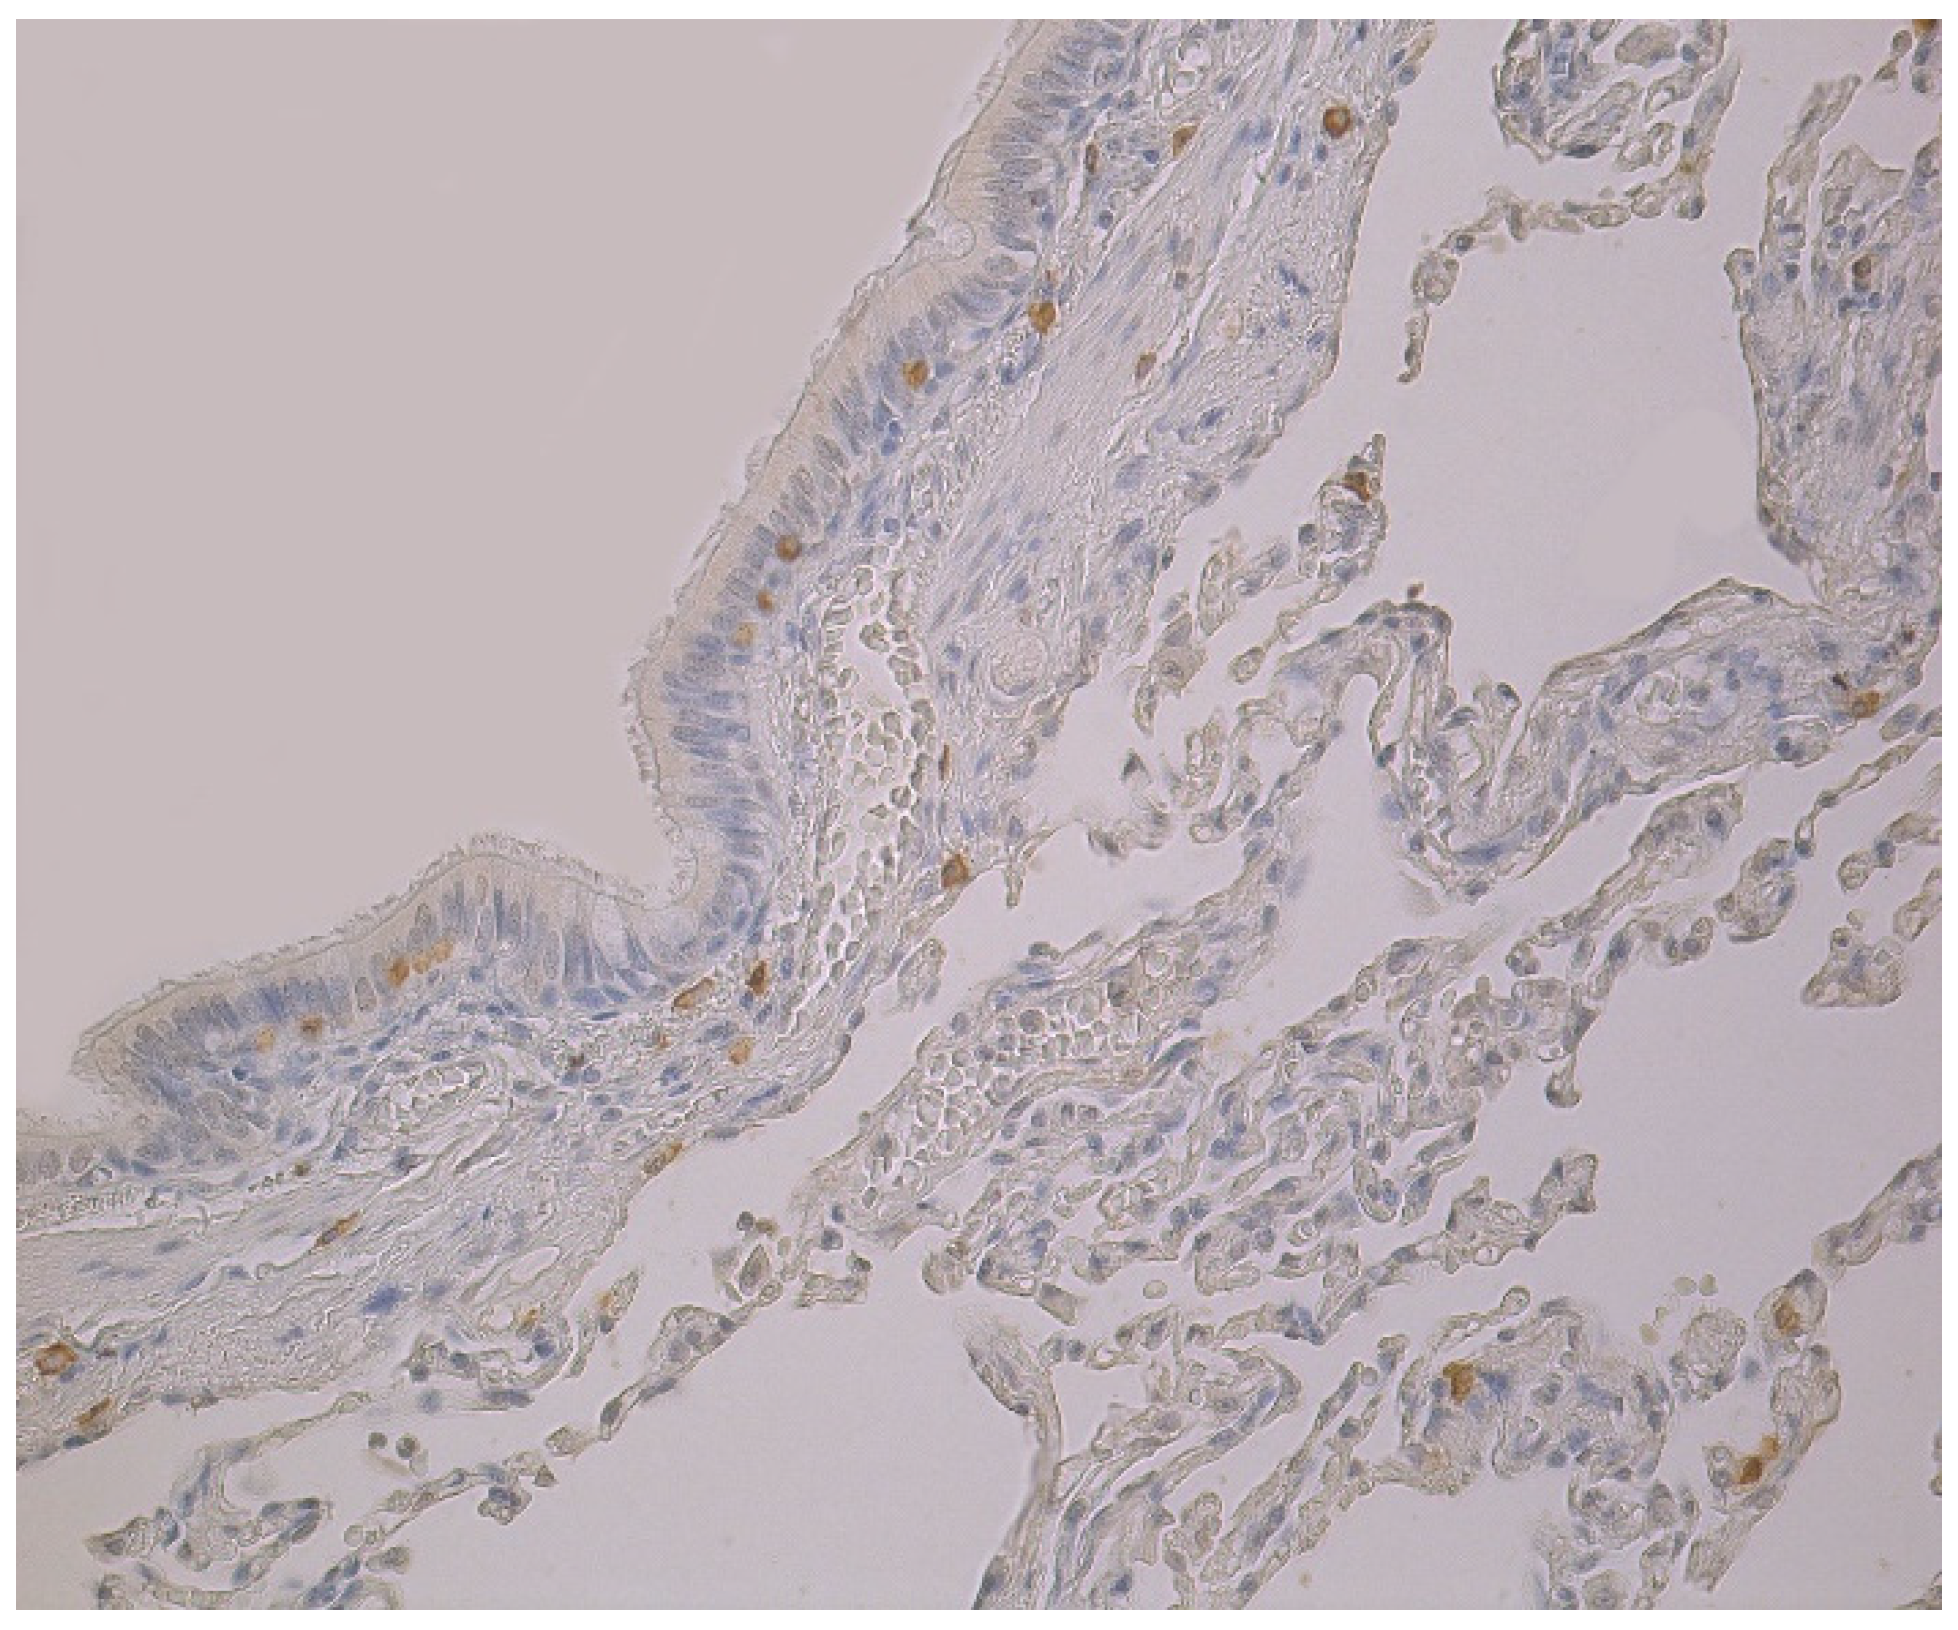

3.1. Tissue Review

3.2. Immunohistochemical (IMH) Data